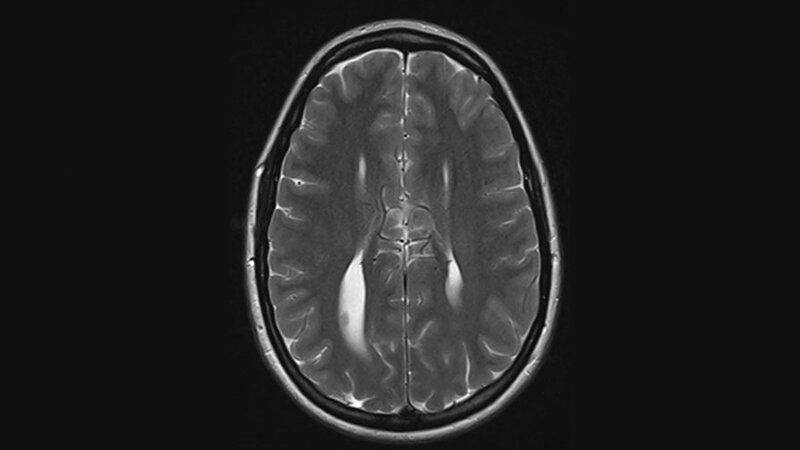

Die Kolpozephalie ist eine angeborene Malformation des Ventrikelsystems des Gehirns. Die Balkenagenesie kann isoliert vorkommen oder in Assoziation mit anderen neuroanatomischen Veränderungen beziehungsweise angeborenen Anomalien.

Schlüsselwörter: Kolpozephalie, Dysgenesie des Corpus callosum, CT, MRT

Colpocephaly is a congenital abnormality in the ventricular system of the brain. Agenesis of corpus callosum may be isolate, or occur in association with other neuroanatomical lesions or congenital anomalies.

Keywords: colpocephaly, dysgenesis of corpus callosum, CT, MRI